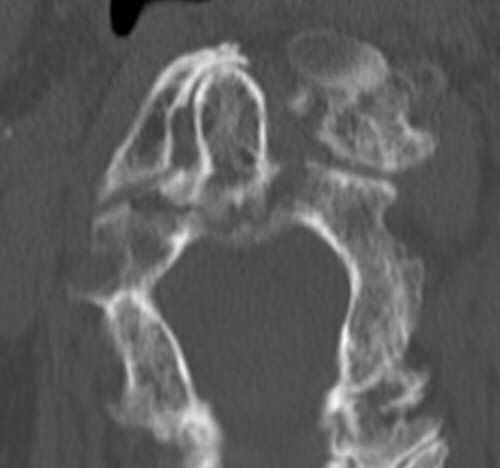

Exempel på dens-fraktur typ 3. Behandlades med halskrage i 12 veckor.